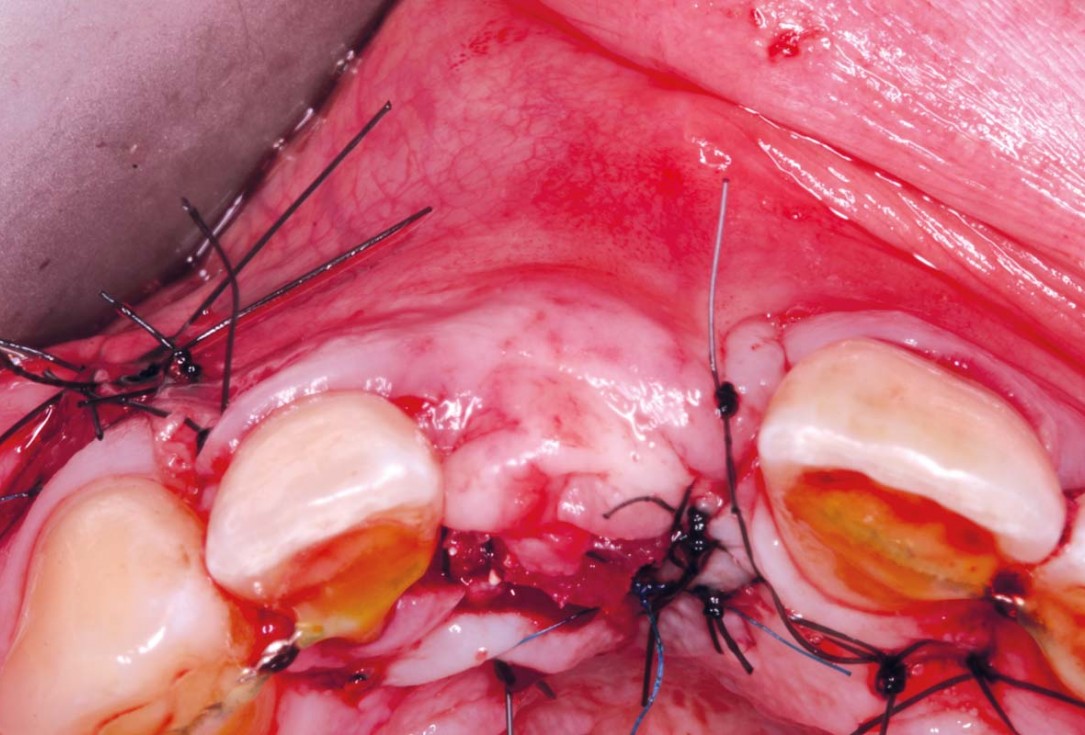

06/20 - Grafting site was covered by two mucoderm® (15x20mm) used as a soft tissue graft as well as a membrane over Jason® membrane . mucoderm® was stabilised with sutures on each side.Delayed implant placement with GBR and soft tissue augmentation at the aesthetic area - 2 years follow up – Dr. H. Maghaireh & Dr. V. Ivancheva

07/20 - Modified sling suture used to stabilise mucoderm® .Delayed implant placement with GBR and soft tissue augmentation at the aesthetic area - 2 years follow up – Dr. H. Maghaireh & Dr. V. Ivancheva

08/20 - Wound closure without tension and without having to make extra incisions.Delayed implant placement with GBR and soft tissue augmentation at the aesthetic area - 2 years follow up – Dr. H. Maghaireh & Dr. V. Ivancheva

09/20 - Wound closure without tension and without having to make extra incisions.Delayed implant placement with GBR and soft tissue augmentation at the aesthetic area - 2 years follow up – Dr. H. Maghaireh & Dr. V. Ivancheva